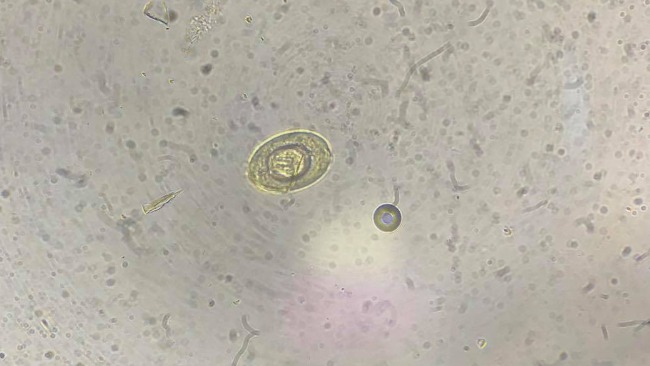

- Oba szczury mają pasożyty wewnętrzne - tasiemce i Giardie, są w trakcie odrobaczania.